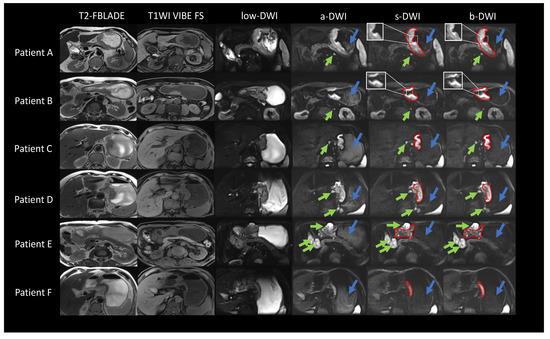

3.2. Image Quality Assessments Results and Analyses

3.3. Ablation Studies for ADCVCGAN